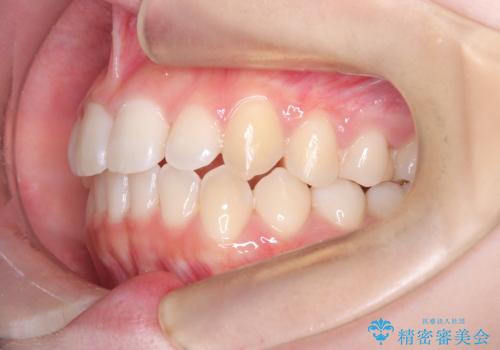

- 右上の前歯(2番)が下の歯より内側に入っている反対咬合を主訴にご来院されました。精密な検査の結果、この反対咬合を解消するためには、右上の歯列に前歯を出すためのスペースを確保する必要があると判明しました。患者様のご希望に合わせ、透明で目立たないインビザライン(マウスピース矯正)による治療計画を立案。奥歯全体を奥へ動かす遠心移動でスペースを作り、反対咬合を解消することを目指します。

今回の矯正治療では、透明なマウスピース型の装置インビザラインを使用しました。治療は、緻密なデジタル計画に基づき、奥歯から順に歯列全体を後方へ移動させる遠心移動を実施し、前歯を前に出すためのスペースを確保しました。このスペースを利用して、内側に入り込んでいた右上2番をスムーズに前方に誘導し、正常な咬み合わせへと改善。目立たないインビザラインで、機能的な咬み合わせと美しい前歯の並びを獲得していただけました。